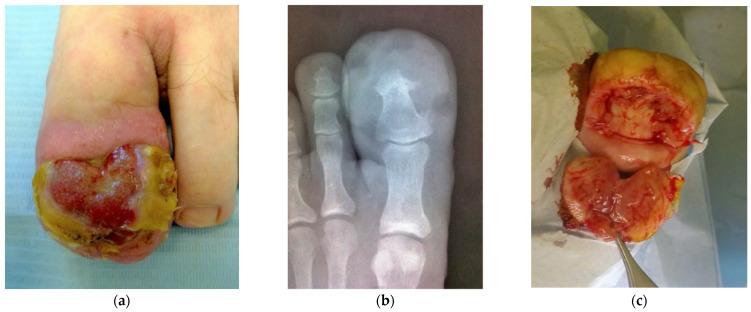

小叶毛细血管瘤(LCH-PG)是一种化脓性肉芽肿,其特征是血管增生,与传统肉芽组织相似。肉芽组织通常与向内生长的脚趾甲有关。尽管两者关系密切,但LCH-PG在临床上表现出不同的行为,如快速生长和频繁复发。目前,尚不清楚不同的病因因素如何导致实体之间的差异形成。我们提出了一个大LCH-PG与慢性甲爪塌陷在一个26岁的男人的情况。组织病理学特征包括广泛的溃疡征象,角化过度,斑块状表皮棘层,溃疡区下方小叶区存在纤维间隔。间质伴血管增生、壁增厚和混合型炎症变化也是其特征。在甲爪隐匿症的晚期,常规肉芽组织或化脓性肉芽肿在临床上很难与其他良性或恶性肿瘤区分。组织学检查是强制性的,切除活检可以提供明确的诊断。

Lobular capillary hemangioma (LCH-PG) is a type of pyogenic granuloma characterized by proliferating blood vessels that resemble conventional granulation tissue. Granulation tissue is very often seen in association with ingrown toenails. Despite the close relationship between both entities, LCH-PG shows clinically different behaviors, such as rapid growth and frequent recurrence. Currently, it is unknown exactly how the different etiological factors contribute to the formation of differences between entities. We present a case of a large LCH-PG associated with chronic onychocryptosis in a 26-year-old man. Histopathological features included extensive signs of ulceration, hyperkeratosis, and patchy epidermal acanthosis with the presence of fibrous septa with lobular areas beneath the ulcerative area. The presence of stroma with a marked proliferation of blood vessels with wall thickening and mixed-type inflammatory changes was also characteristic. In advanced stages of onychocryptosis, as presented here, conventional granulation tissue or pyogenic granuloma can be clinically difficult to distinguish from other benign or malignant neoplasms. Histological examination is mandatory, and excisional biopsy can provide a definitive diagnosis.